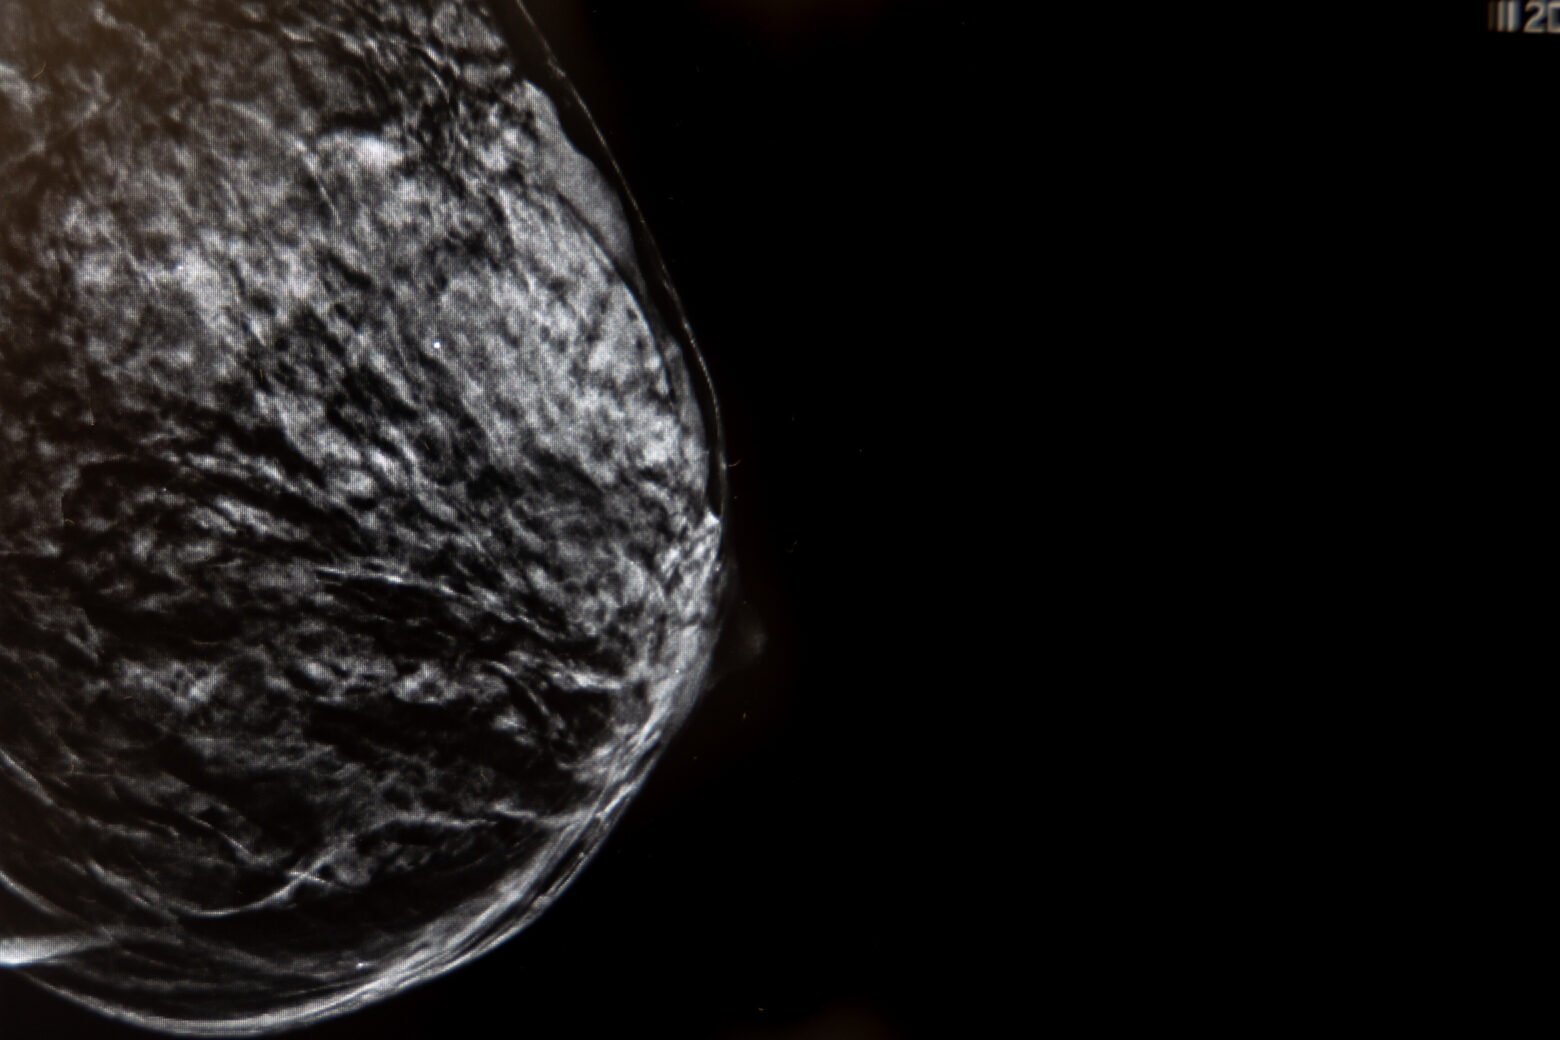

La radiología de mama, principalmente la mamografía, es una técnica de imagen que utiliza rayos X para detectar anomalías en el tejido mamario, siendo fundamental para el cribado y la detección temprana del cáncer de mama.